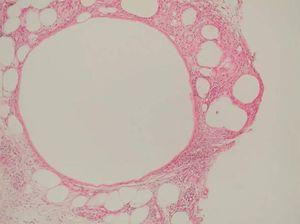

Desde el punto de vista histopatológico, se observó en todos los casos la formación de estructuras membranosas hialinas, eosinófilas, amorfas, anucleares, que revestían espacios quísticos de tamaños variables, localizadas en el interior de los lobulillos del tejido celular subcutáneo. Estos quistes estaban revestidos por una membrana hialina gruesa (fig. 4) o se observaban proyecciones paralelas o en arabesco de membranas hialinas (figs. 5 y 6). También se observó depósito de material lipomembranoso en áreas de fibrosis septal. Las membranas mostraban una intensa positividad con la tinción de PAS y eran diastasa-resistentes. En algunos casos se observaba una reacción granulomatosa alrededor de los espacios quísticos (fig. 7). En uno de los casos se observó un infiltrado neutrofílico en el espesor de la pared de los espacios quísticos (fig. 8), que correspondía a necrosis de adipocitos.

Fig. 4.--HE, x40. Espacios quísticos dimensiones variables revestidos por membrana hialina engrosada.

En seis biopsias (casos 1-5 y 7) se observaban signos de dermatitis de estasis (fig. 9) en la dermis superficial, caracterizados por una proliferación vascular, con vasos de paredes gruesas ocupando la dermis papilar, entremezclados con un infiltrado linfocitario y depósitos de hemosiderina (figs. 6 y 10).

Fig. 9.--PAS-D; x10. Dermatitis de estasis.